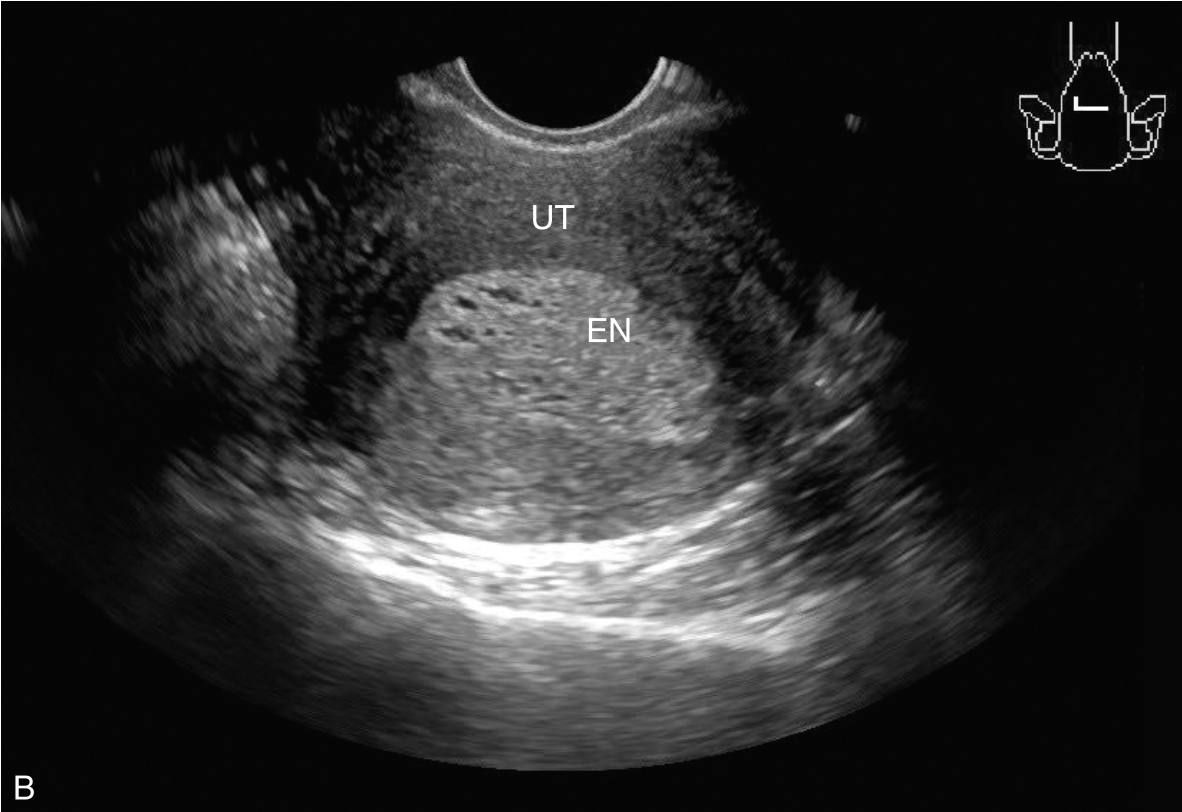

经阴道超声检查见图3-5-1。子宫后位,宫体大小约5.8cm×5.0cm×5.1cm,宫内膜厚约0.75cm(单层),内膜回声不均匀。宫腔未见分离。宫壁回声均匀。内膜内见多个囊性结节,较大者大小约0.5cm,内透声可。CDFI:未见异常血流信号。双侧附件区未见异常回声。盆腹腔未见明显积液。超声检查结果:宫内膜增厚伴回声不均匀。

图3-5-1 常规超声声像图

A.后位子宫的矢状切面(经阴道),子宫内膜增厚,单层厚约0.75cm,内见多个小暗区;B.后位子宫的横断面(经阴道);C.后位子宫的矢状切面(经阴道),彩色多普勒能量图超声检查显示子宫未探及明显血流信号;D.右卵巢;E.左卵巢。UT:子宫;EN:子宫内膜;R-OV:右卵巢;L-OV:左卵巢。